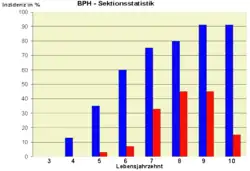

Die BPH ist der häufigste gutartige Tumor beim Mann. In den ersten Lebensjahrzehnten des Mannes ist sie sehr selten, ab dem 6. Lebensjahrzehnt findet sich jedoch bei 50 % aller Männer eine Vergrößerung der Prostata. Die Krankheitshäufigkeit steigt bis auf über 90 % im 9. Lebensjahrzehnt. Das Risiko, daran zu erkranken, liegt bei 10–20 % in der Altersgruppe 50 bis 59 Lebensjahre und 25–35 % in der Altersgruppe von 60 bis 69 Jahre.[7] Aufgrund ihrer hohen Krankheitshäufigkeit gilt die BPH als Volkskrankheit.